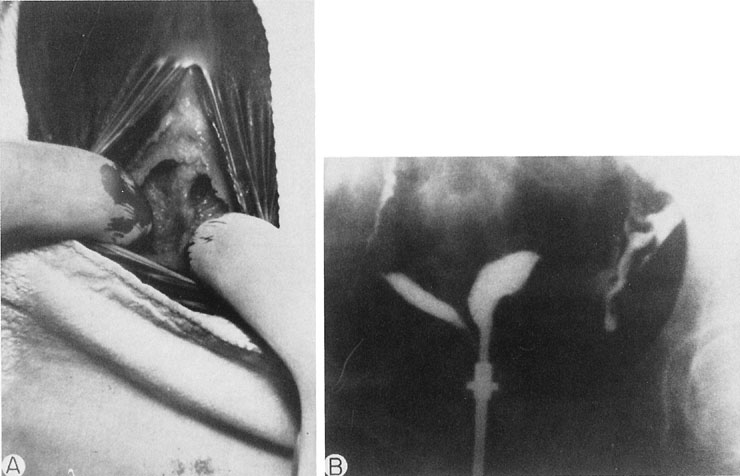

The persistent hymen should be mentioned, although it is not included as a disorder of vertical fusion. The hymen consists of a membrane separating the vaginated caudal end of the fused paramesonephric ducts from the evaginated urogenital sinus. The hymen may persist if centrally placed epithelial cells do not degenerate and produce the expected hymenal remnants. With accumulated menstrual blood, a bulge in the hymen is often recognized (Fig. 8). The hymen may be excised with a cruciate incision.

Fig. 8. A. A partially obstructed persistent hymen. B. A persistent hymen with a bulge due to accumulated menstrual blood. C. After the hymenal membrane is incised in a cruciate fashion, a large amount of accumulated menstrual blood is evacuated.(Jones HW Jr, Baramki TA: Congenital anomalies. In Kistner R, Behman J [eds]: Progress in Infertility, p 77. Boston, Little, Brown, 1968)